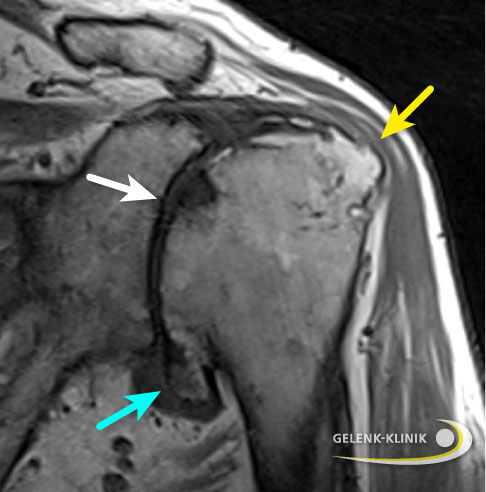

Kernspintomographie (MRT): Darstellung der Weichteile

Die MRT-Untersuchung unterstützt den Spezialisten dabei, die Weichteilstrukturen der betroffenen Schulter, insbesondere die Sehnen der Rotatorenmanschette, zu beurteilen. Funktion und Stabilität des Schultergelenks werden durch die Einheit von Muskeln und Sehnen der Rotatorenmanschette gewährleistet.